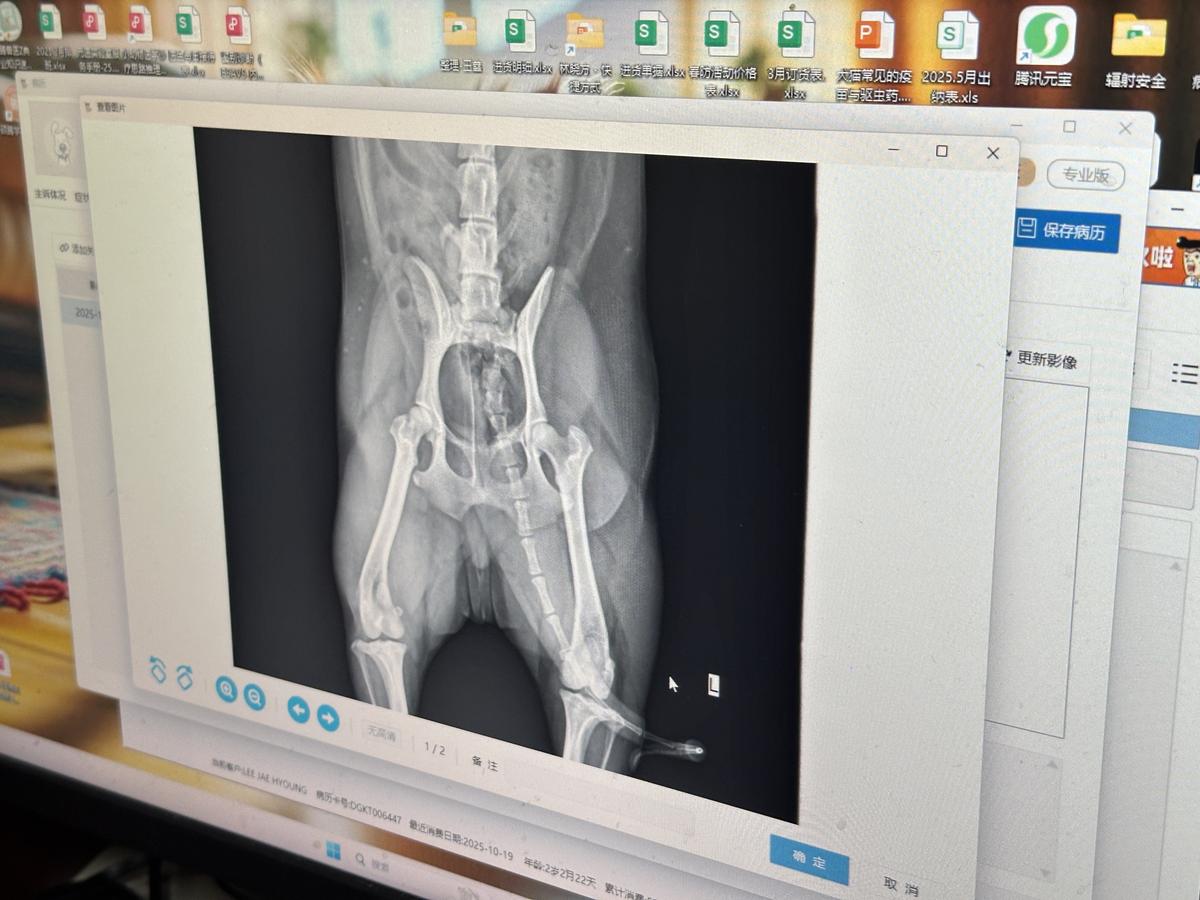

슬개골 탈골 X-Ray 판단부탁드립니다(수술 필요 여부 포함)

안녕하세요, 저는 해외에서 강아지를 키우는 사람입니다. 저희가 키우는 집 환경이 대리석 바닥으로 되어 있습니다. 4주전에 퇴근 후 집에 왔을때 강아지가 흥분한 상태에서 바닥에 있던 인형을 물고 올려고 턴을 하는 순간 미끌리면서 ”끼깅“ 소리를 내고 뒷쪽 오른 다리를 들고 걷기 시작하였습니다. 이런 상황이 처음이라 너무 놀라서 일단 다리를 폈다 오르렸다를 했더니 ”뚝“하는 소리가 났고 그 후 정상적으로 걷기 시작하였고 일주일정도 경과를 보다 동물 병원에 가서 X-Ray 검사를 받았는데, 왼쪽 뒷다리는 슬개골 탈골 2기, 들고 걸었던 오른 다리는 3기를 향해 가고 있다는 진단을 들었습니다. 그리고 3일전에 똑같은 상황이 또 발생하였고, 빠졌다 들어갔다가 반복이 되는거 같습니다..ㅠㅜ 저의 무지함으로 인해 어릴때부터 바닥 매트없이 대리석 바닫에 키워 그렇게 된거 같아 강아지에게 미안한 마음뿐입니다. 현재 수술을 고려하고 있는데 해외에서 검사를 받은 부분이라 좀 더 정확한 판단을 받기 위해 당시 촬영했던 X-Ray사진, 수술 진행 필요 여부를 문의드립니다. 감사합니다